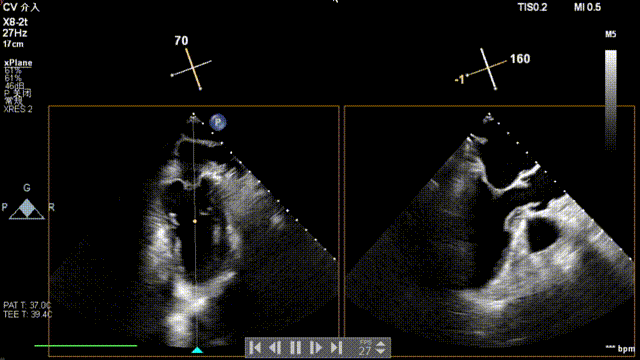

全麻后,二尖瓣夹合器系统在心前区的肋间切开3-4CM小切口,暴露心脏的心尖位置,送系统送入左心房,顺利到达病变二尖瓣区域。在经食道超声辅助下,术者通过反复评估二尖瓣反流位置、抓捕位置、反流程度,首先在2偏3区位置处于二尖瓣闭合线垂直进行巧妙夹合。在2区靠近3区位置处植入了1枚ValveClamp®MVC-IIf夹,最终评估评估反流降至轻度,平均跨瓣压差降至2mmHg,手术取得圆满成功。

术中超声(关键步骤)

术后超声

最终在A3P2位置夹合,前叶夹合量10mm,后叶夹合量8mm,剩余瓣口面积3.45cm²,平均跨瓣压差2mmHg,反流基本消除。